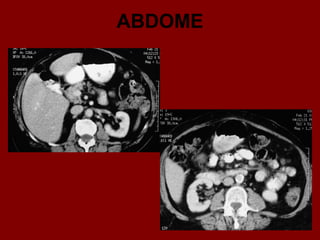

ABDOME

Ac Colo ascendente AP Nível de ar fluido do estômago Ao Aorta Az Veia ázigo CA Tronco celíaco cc Cartilagem costa! CD Dueto cístico CHA Artéria hepática comum CHD Dueto comum CL Lobo caudado fígado D Diafragma DBM Músculos profundos do De Colo descendente D2 Parte descendente do duodeno D3 Parte horizontal do duodeno E Esôfago FL Ligamento falciforme GB Vesícula biliar HA Artéria hepática Hz Veia IMV Divisão da veia mesentérica inf. A IVC Veia cava inferior LC Ramo esq. do diafragma LG Glândula supra-renal esq. LHV Veia hepática esquerda LIL Lobo inf. Esq. do pulmão LRV Veia renal esquerda LK Rim esquerdo LU Ureter esquerdo LL Lobo esquerdo do fígado MHV Veia hepática média P Pâncreas PA Antro pilórico do estômago

Ac Colo ascendente AP Nível de ar fluido do estômago Ao Aorta Az Veia ázigo CA Tronco celíaco cc Cartilagem costa! CD Dueto cístico CHA Artéria hepática comum CHD Dueto comum CL Lobo caudado fígado D Diafragma DBM Músculos profundos do De Colo descendente D2 Parte descendente do duodeno D3 Parte horizontal do duodeno E Esôfago FL Ligamento falciforme GB Vesícula biliar HA Artéria hepática Hz Veia IMV Divisão da veia mesentérica inf. IVC Veia cava inferior B LC Ramo esq. do diafragma LG Glândula supra-renal esq. LHV Veia hepática esquerda LIL Lobo inf. Esq. do pulmão LRV Veia renal esquerda LK Rim esquerdo LU Ureter esquerdo LL Lobo esquerdo do fígado MHV Veia hepática média P Pâncreas PA Antro pilórico do estômago